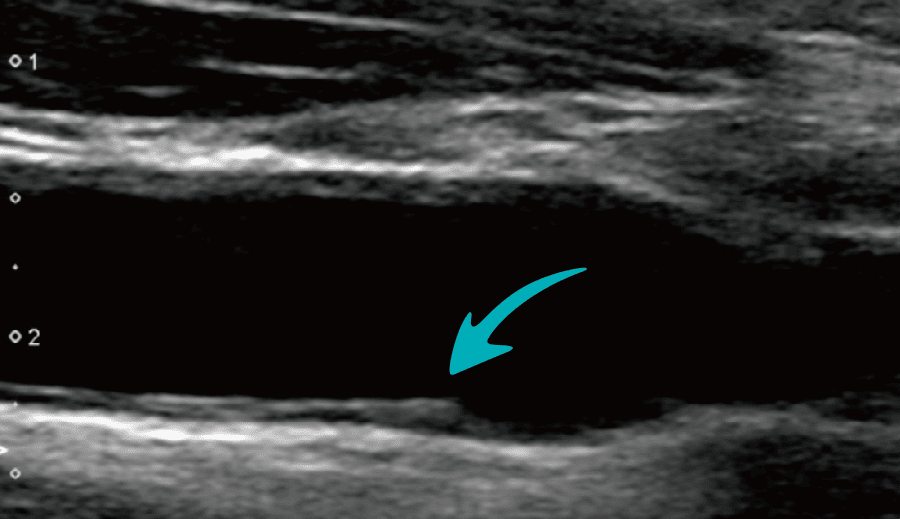

内膜中膜複合体(IMT)肥厚

動脈は内膜、中膜、外膜の3層からなり、血管の内側にあたる内膜と中膜の厚さを計測した数値をIMT「内膜中膜複合体厚(Intima Media Thickness)」といいます。動脈硬化は加齢によって進行するため、IMTも年齢とともに厚くなる傾向ですが、1.1mm以上を肥厚と診断しています。